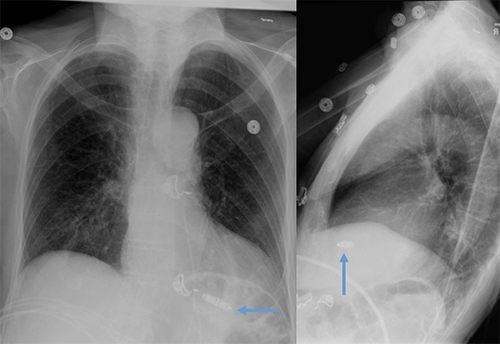

- CEID images with lead types:

Pacemaker with transvenous leads

Pacemaker with epicardial leads

Defibrillator lead

Subcutaneous defibrillator

Cut epicardial wires (often hard to see)

Abandoned leads

Abanded leads plus generator

Temporary transvenous lead

Leadless pacemaker